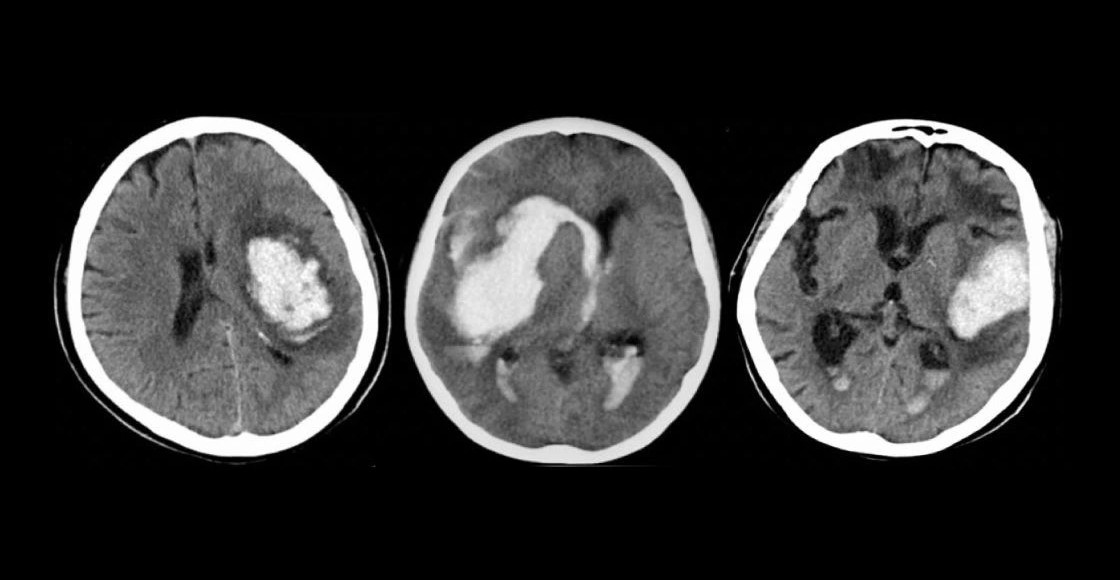

Un derrame cerebral es un evento en el que un vaso sanguíneo del cerebro se rompe y sangra dentro, aumentando la presión en el cráneo, causando inflamación del tejido cerebral y dañando las células. Se necesita atención médica de emergencia.

Y s que si una hemorragia cerebral no se trata a tiempo, las lesiones cerebrales pueden llevar a los pacientes a la muerte o a dejarlos con lesiones graves que tienen como consecuencia una discapacidad.